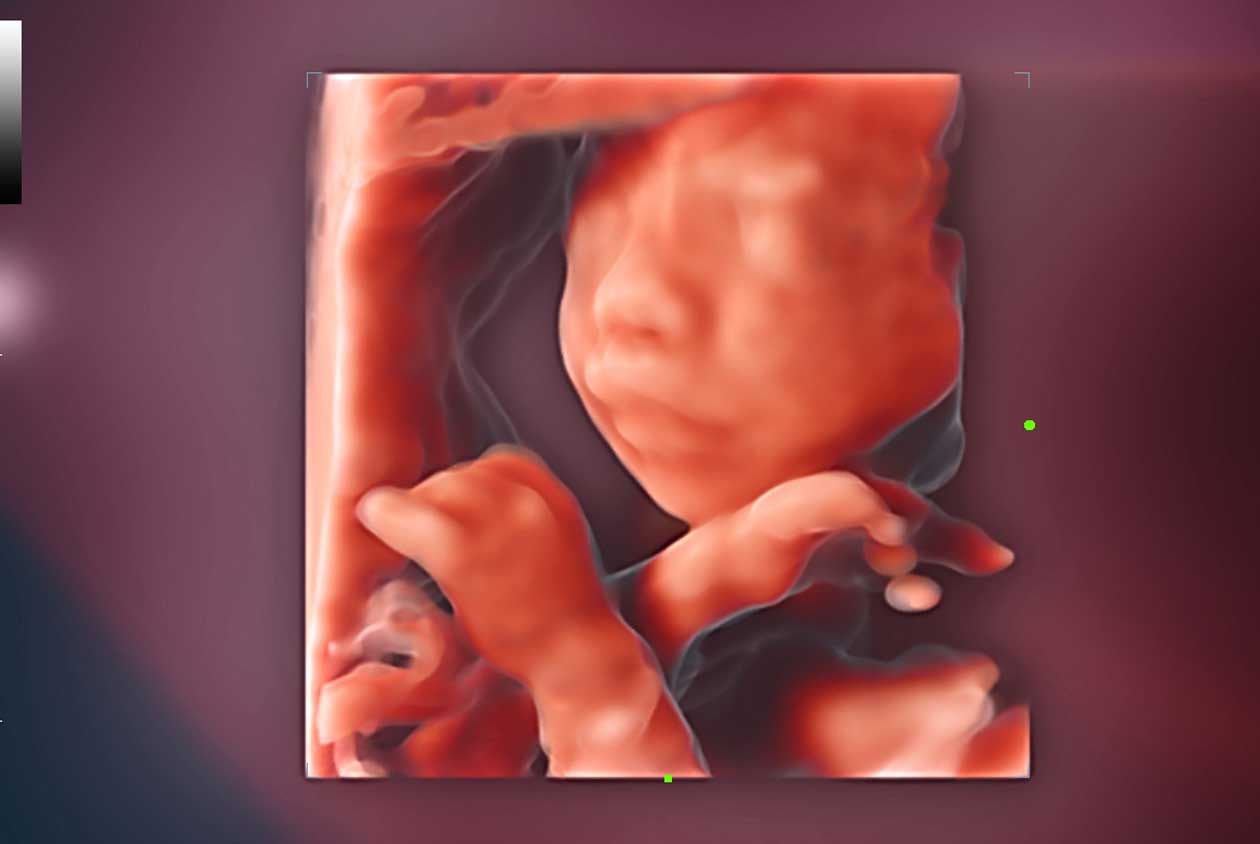

Clinical Images